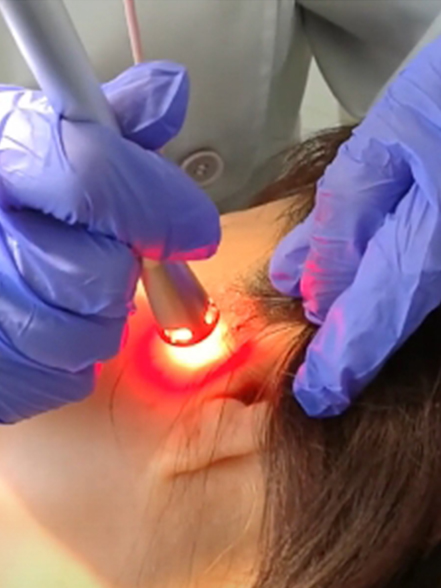

AZUL 450 nm

A 450 nm se alcanza el pico de máxima absorción de la hemoglobina, lo que permite un corte y una coagulación eficientes sin contacto a muy baja potencia, minimizando al mismo tiempo el daño térmico.

ROJO 650 nm

Terapia láser de baja intensidad (LLLT) / Fotobiomodulación para una cicatrización más rápida de las heridas y tratamientos dentales sin dolor.

IR 810/980 nm

Las longitudes de onda infrarrojas de 810/980 nm proporcionan una penetración profunda para una desinfección excepcional en tratamientos periodontales, endodóncicos y de implantes. Su excelente absorción por el agua mejora la ablación tisular, garantizando resultados de tratamiento eficaces y precisos.

Soporte clínico más completo en un solo sistema.